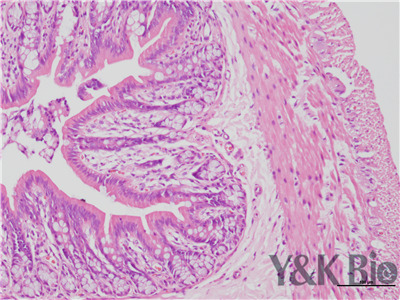

HE染色流程是什么,很多人都不知道,今天跟着小编一起来学习一下,切片的好坏直接影响疾病诊断的及时与准确性。因此一张高质量的HE染色切片,是实验室必须掌握的技术之一。HE染色目前在国内国外病理诊断上被

广泛采用,常规的染色方法。下面一起来看HE染色的基本顺序。一般切片的片子应在60-70度左右的烤箱中烘烤30分钟以才可以进行染色。总的来说是一个时间较长的过程。

1.样品制备

对于贴壁生长细胞,胰酶消化,调整细胞浓度约1×105/ml,滴加于盖玻片上(置于6孔板中),培养相应时间后,取出细胞爬片,用PBS 洗涤3次。2.样品固定 95%乙醇固定20min,PBS洗涤2次,每次1min。3.染核 苏木

素染液染色2-3min,自来水洗涤。4.分色 镜下观察,若细胞核染色过深,用1%盐酸酒精溶液分色数秒,自来水洗涤。 5.染胞质 浸入伊红染液染色1min,自来水洗涤。6.封片 吹干或自然晾干细胞爬片后,重庆中性树胶封片。

以上六点就是HE染色的基本步骤,大家可以参考一下哦 。